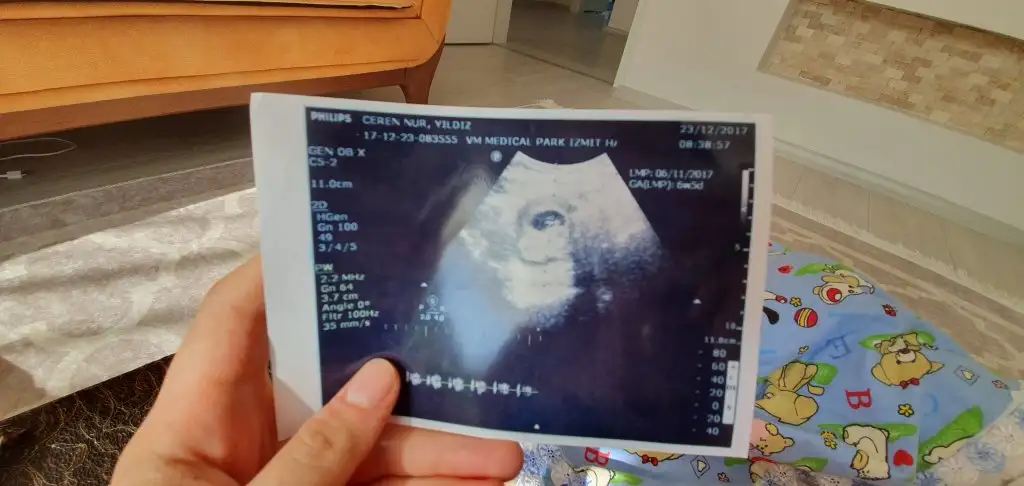

Bu benim 5.hafta vajinal ultrasonum ilk fotoğraftaki. altta 6. hafta diyor ama benim 1 hafta geç döllenme.

2.foto 6.hafta karından ultrason.